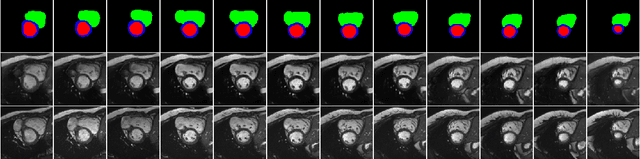

Abstract:We propose a method for synthesizing cardiac MR images with plausible heart shapes and realistic appearances for the purpose of generating labeled data for deep-learning (DL) training. It breaks down the image synthesis into label deformation and label-to-image translation tasks. The former is achieved via latent space interpolation in a VAE model, while the latter is accomplished via a conditional GAN model. We devise an approach for label manipulation in the latent space of the trained VAE model, namely pathology synthesis, aiming to synthesize a series of pseudo-pathological synthetic subjects with characteristics of a desired heart disease. Furthermore, we propose to model the relationship between 2D slices in the latent space of the VAE via estimating the correlation coefficient matrix between the latent vectors and utilizing it to correlate elements of randomly drawn samples before decoding to image space. This simple yet effective approach results in generating 3D consistent subjects from 2D slice-by-slice generations. Such an approach could provide a solution to diversify and enrich the available database of cardiac MR images and to pave the way for the development of generalizable DL-based image analysis algorithms. The code will be available at https://github.com/sinaamirrajab/CardiacPathologySynthesis.